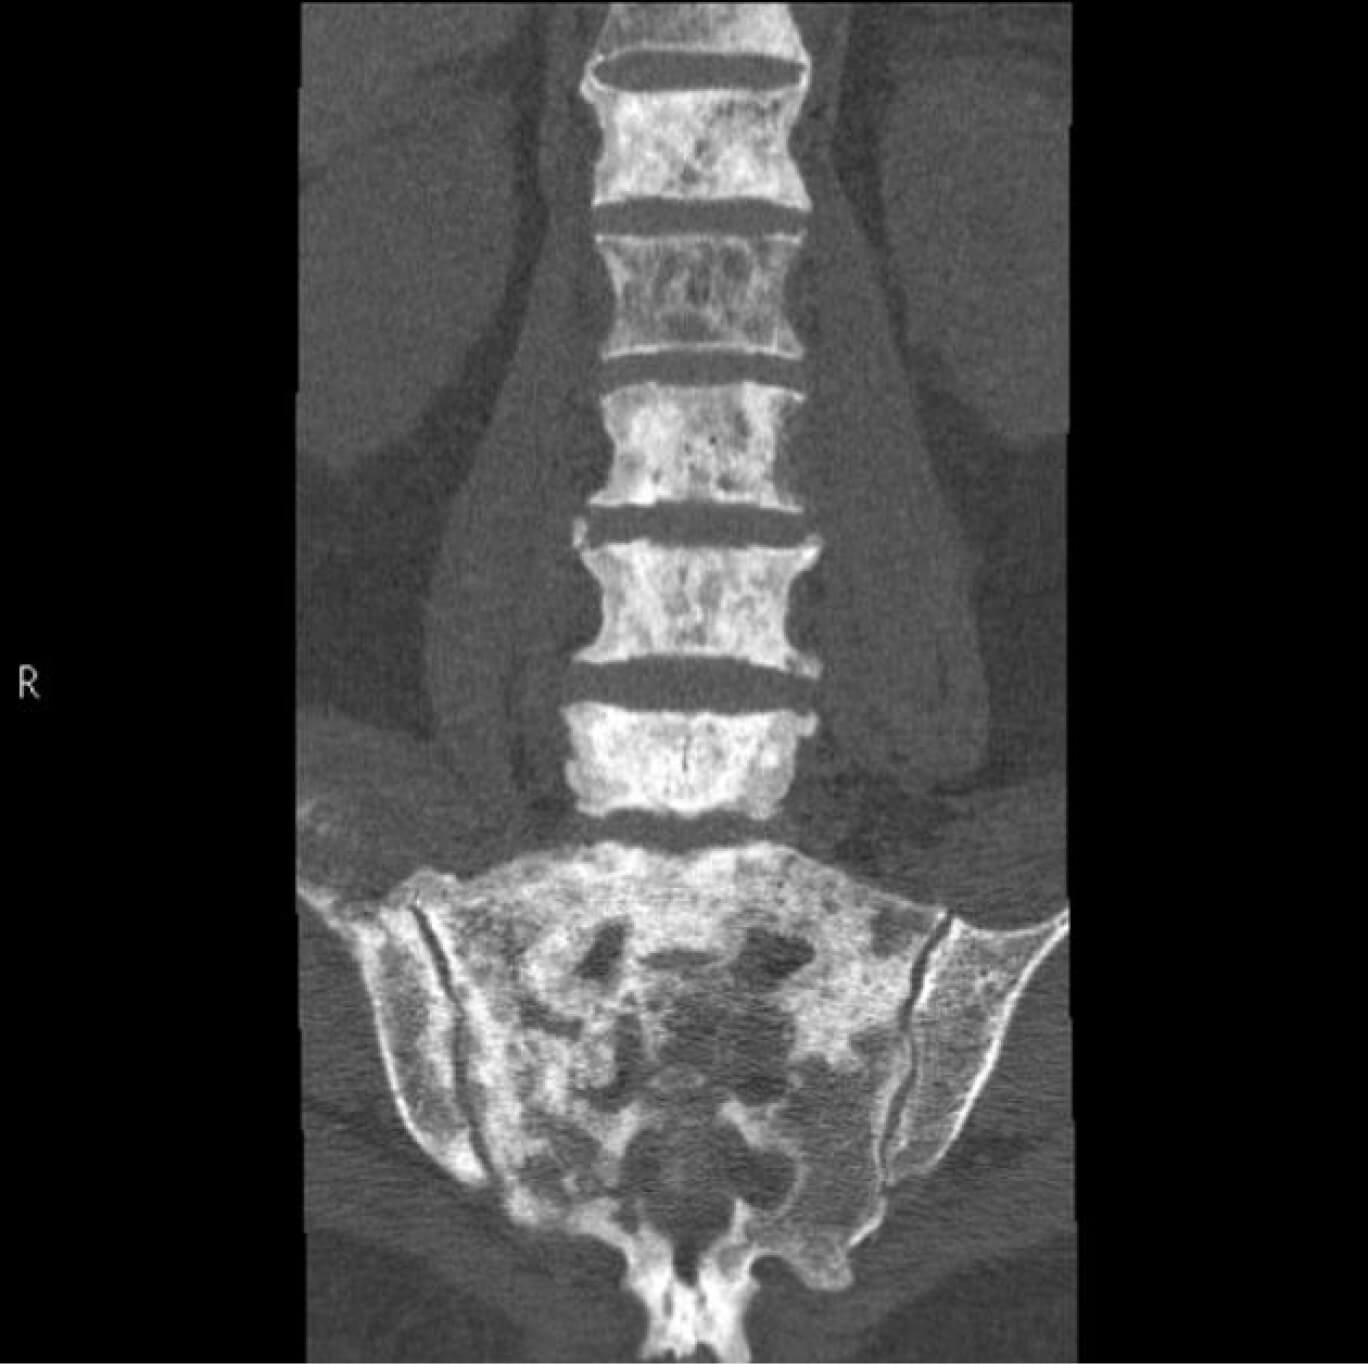

Результаты УЗИ молочных желез и регионарных лимфоузлов, указывают, вероятнее всего, на злокачественную природу новообразования:

образование молочной железы имеет неоднородную структуру, неровные и несимметричные края

регионарные лимфатические узлы увеличены в размерах по короткой оси

Рис. 1 — результаты УЗИ молочных желез и регионарных лимфоузлов. На слайде слева новообразование молочной железы. Отмечается неоднородность новообразования, неровность и несимметричность краев. На слайдах справа — фрагменты с изображением двух регионарных лимфатических узлов. На злокачественность изменений намекает увеличение размеров лимфоузлов по короткой оси.